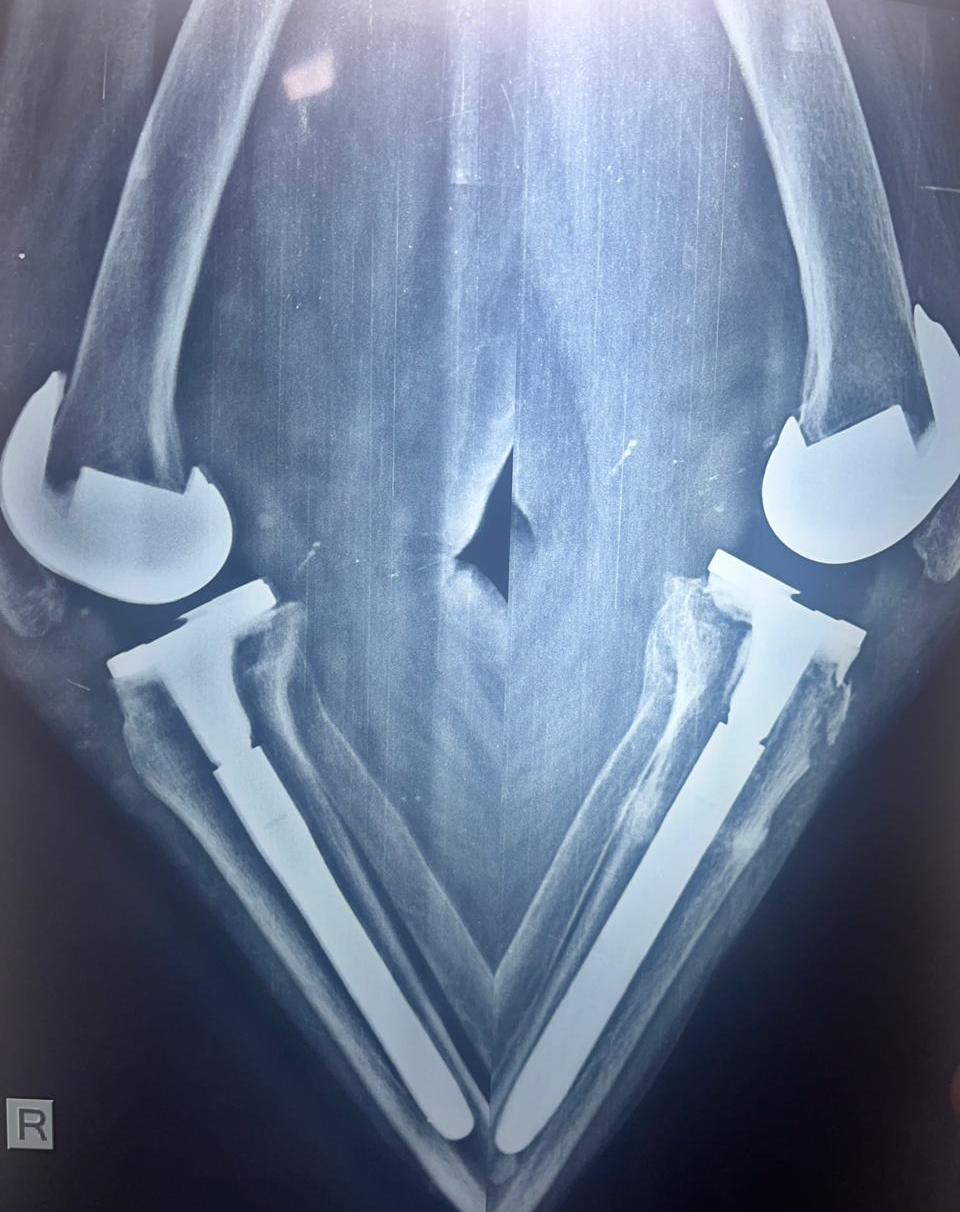

72 years female patient did not walk for 3 months suffered stress fracture of tibis on left side . Bilateral toral knee replacement done with extension rods